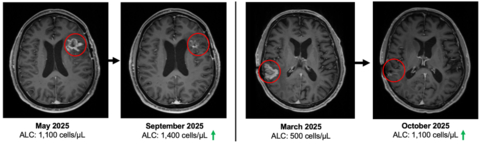

Figure 1

QUILT-3.078 enrolled patients with recurrent GBM at first recurrence. In the spIND population, seven patients were first line and are alive to date. Randomized clinical trials for both first line and second line+ GBM patients are in development.

As of January 22, 2026, the study has enrolled 23 patients with recurrent or progressive GBM who progressed following standard-of-care therapy, including surgery, radiation, and temozolomide-based chemotherapy. 19 of the 23 enrolled patients remain alive, with four deaths reported to date. See figure 1.